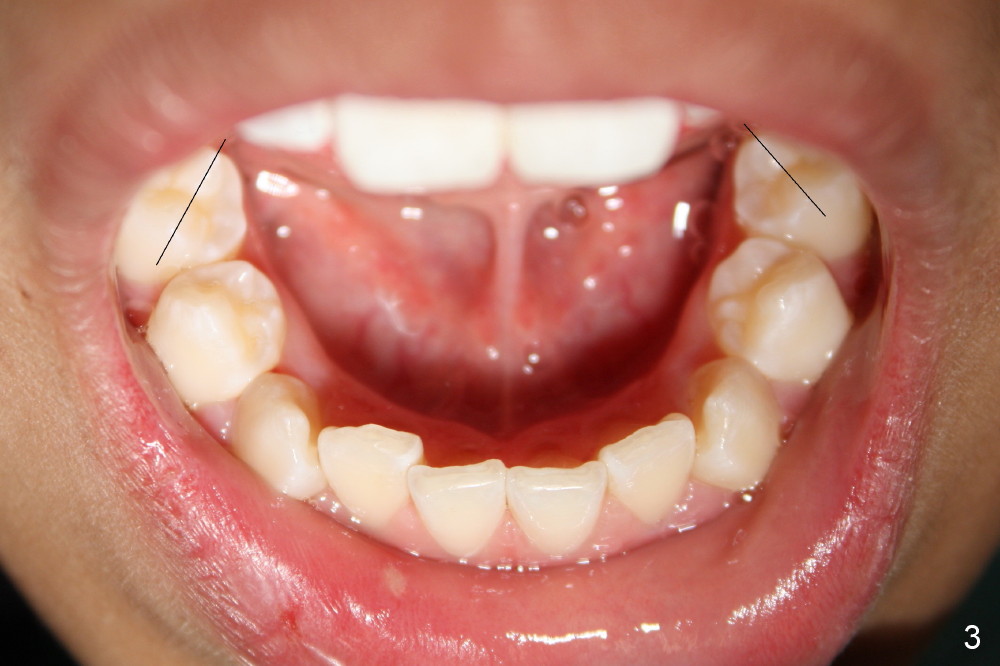

Crowding & Rotation

Joshua, 11 years old, has dental crowding (Fig.1), particularly in the lower arch (Fig.3) with molar Class I relationship (Fig.2). The lower 5s rotate (Fig.2 black lines), which are corrected with power chains (Fig.4,5) after bracketing and placing .012" niti wires (Fig.6).